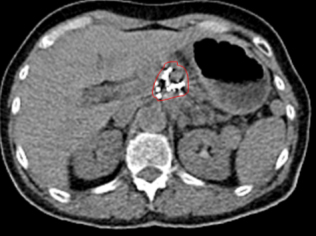

比瑞特的CT图示治疗前胰腺头体部巨大肿瘤,活检腺癌

治疗后10个月复查CT,显示病变显著缩小,PET上无活性,提示肿瘤坏死